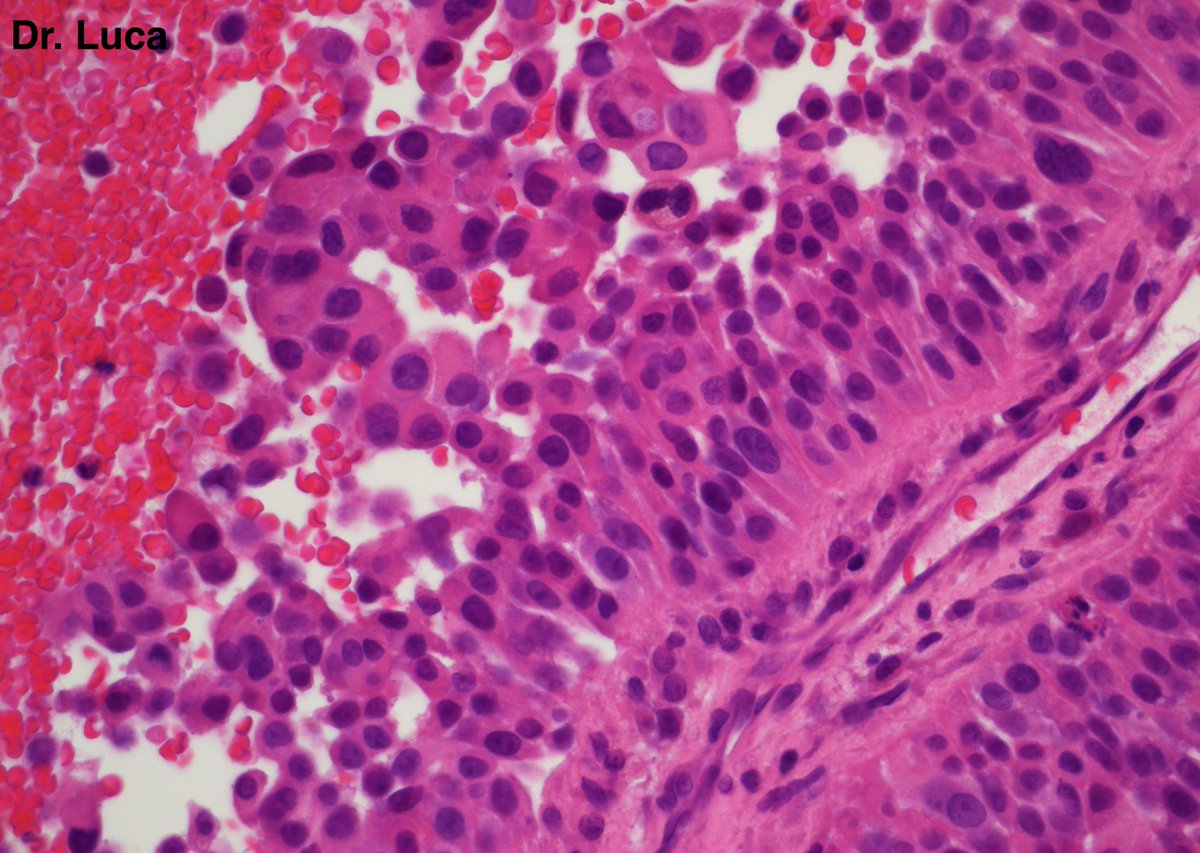

@Pathmath1 @SumantaDas_7 @PoloniaAntonio @ivanaspath @AnapathResident @bansar7 @goziemnweke @Teclis82 @Dr_Brian_Cox @DrBMcGinn @ariella8 @nusrat_xahra @DrRusella_Mirza @glinglerimek @kis_lorand @Venkateshgilly2 @DrBonita16 @DrPayelMondal @DrGeeONE @anjuthevirgo @niki_2389 @pepeheffernan @AngeloCassisa @NeoCrazee @TristanRutland7 Yes, it's a cancer with PNI...I show you the "superficial" layer of this cancer...what is the cancer? and what is the organ? #Pathology #GIpath #PathTwitter #PathResidents #pathboards